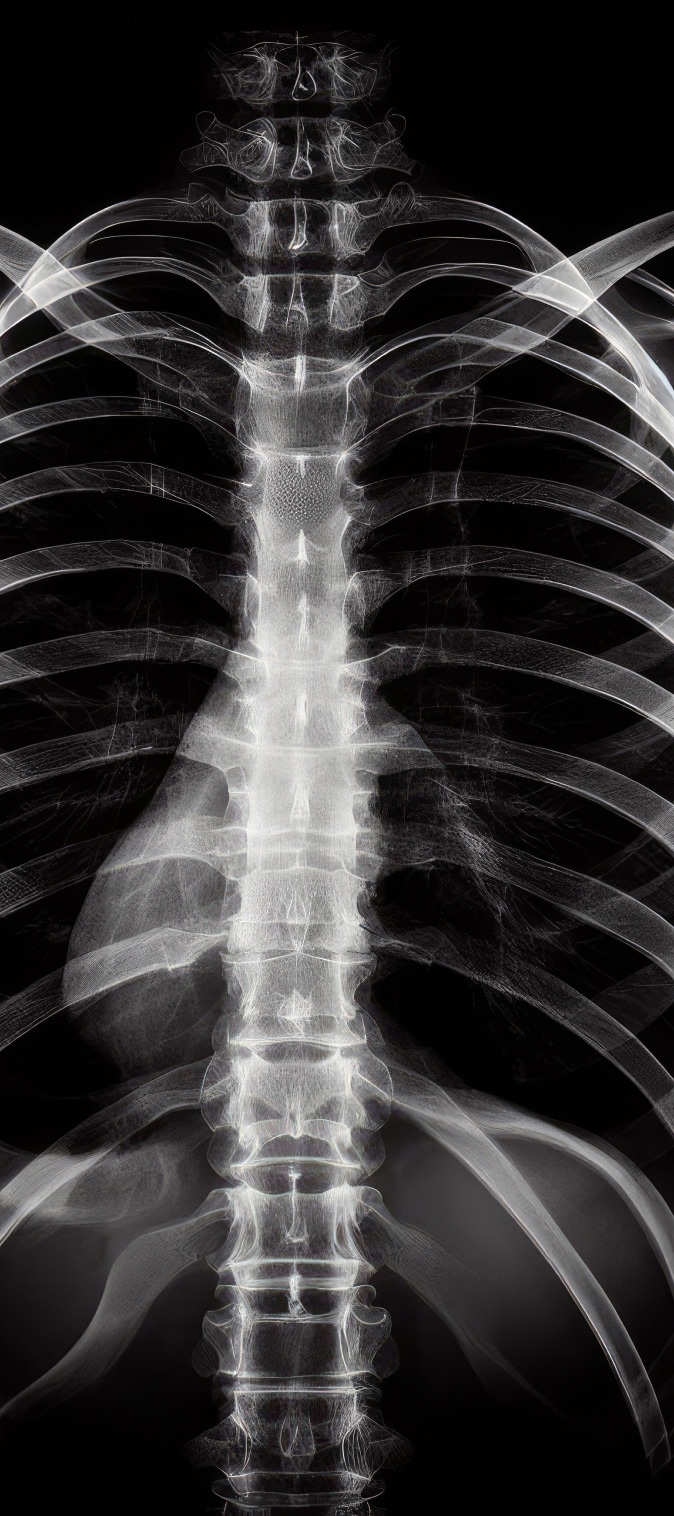

El pectus excavatum, conocido como pecho hundido, y el pectus carinatum, denominado pecho salido, son malformaciones congénitas de la pared torácica presentes desde el nacimiento. Aunque en algunos casos pueden pasar desapercibidas durante la infancia, estas deformidades tienden a acentuarse con el crecimiento, especialmente durante la adolescencia, etapa en la que el desarrollo óseo y cartilaginoso es más acelerado.

El pectus excavatum, conocido como pecho hundido, se caracteriza por una depresión del esternón hacia el interior del tórax. Esta condición puede reducir el espacio disponible para los pulmones y el corazón.

El pectus carinatum, o pecho salido, se manifiesta por una protrusión anormal del esternón hacia adelante. Aunque suele afectar menos la función respiratoria, puede producir dolor torácico, incomodidad al realizar actividad física y una alteración visible de la forma del pecho.

El pectus mixto combina características del pectus excavatum y del pectus carinatum. En estos casos, el tórax presenta zonas hundidas y otras sobresalientes, lo que genera una deformidad más compleja que requiere una evaluación especializada para definir el mejor tratamiento quirúrgico.

Las malformaciones torácicas como el pectus excavatum, el pectus carinatum y el pectus mixto se producen principalmente por un crecimiento anormal de los cartílagos costales. Este crecimiento irregular empuja el esternón hacia adentro o hacia afuera, alterando la forma normal del tórax.